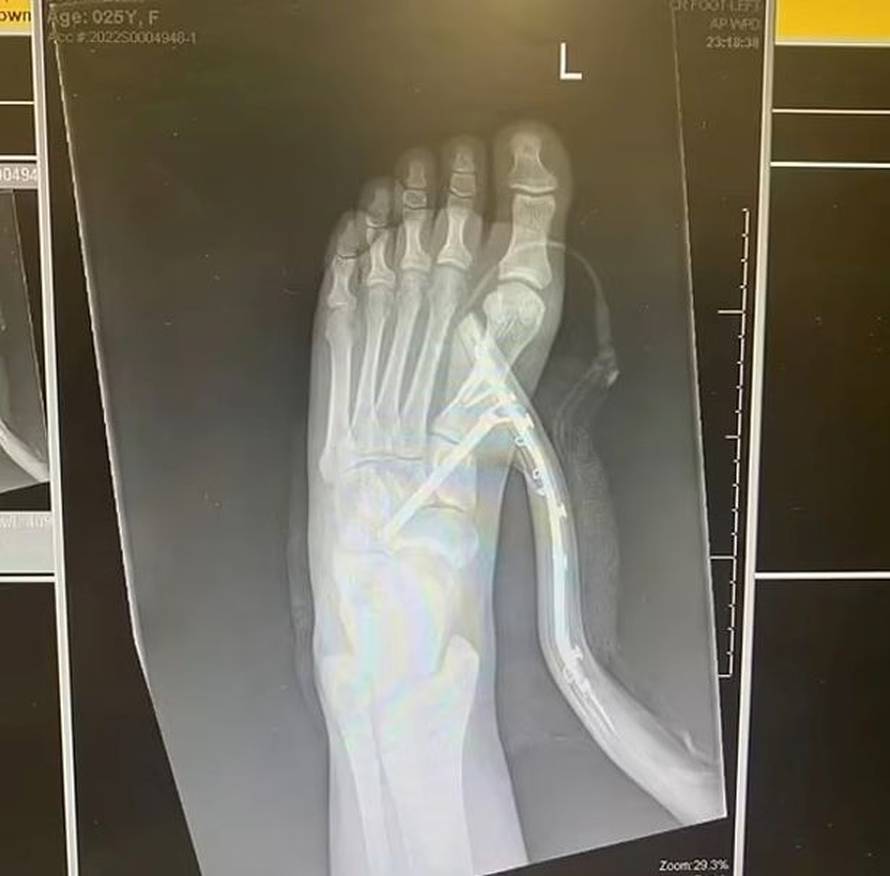

Pozvala je cimericu kako bi joj izvadila petu iz stopala, no ona je odbila i pozvala hitnu pomoć.